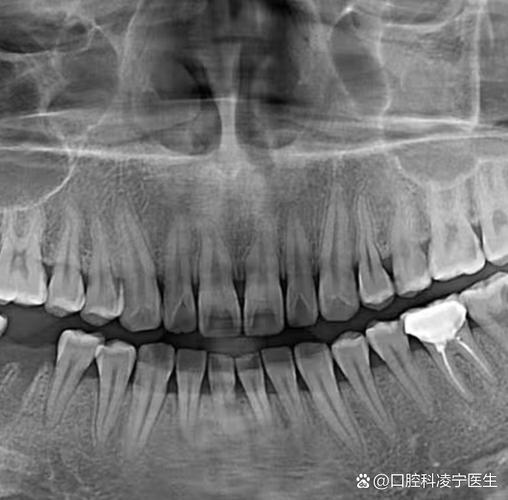

全景片(曲面断层片)

全景片是矫正牙齿最基础的检查,可一次性显示全口牙齿、牙槽骨、颌骨及周围重要解剖结构(如上颌窦、下颌神经管),其主要作用包括:

- 牙齿发育情况:观察牙齿数量(是否存在多生牙、缺失牙)、形态(如过小牙、锥形牙)、位置(如牙齿是否萌出、阻生)及牙根形态(有无弯曲、吸收)。

- 牙槽骨状况:评估牙槽骨高度、密度,是否存在骨缺损、囊肿或肿瘤等病变。

- 颌骨关系:初步判断上下颌骨的位置关系,如下颌是否偏斜、颞下颌关节是否有异常(如髁突形态改变)。

- 第三磨牙情况:判断智齿位置、方向及对相邻牙齿的影响,尤其是对需要拔牙矫正的患者,可提前规划拔牙方案。

注意事项:全景片为二维影像,存在重叠干扰,对细小结构(如牙根吸收、邻面龋)的分辨率有限,需结合其他检查补充。